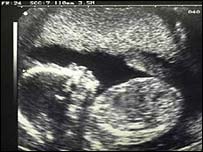

ماہرین کا کہنا ہے کہ طبی معائنے یعنی الٹراساؤنڈ کے ذریعے پیدائش سے قبل بچوں کی جنس معلوم کرنا دیہاتوں میں عام بات ہوگئی ہے اور اگر اس روِش کو نہیں روکا گیا تو لگ بھگ سات ملین لڑکیاں آئندہ دو عشروں میں ماری جائیں گی۔

الٹرا ساؤنڈ کے ذریعے پیدائش سے قبل بچوں کی جنس معلوم کرنا عام ہوگیا